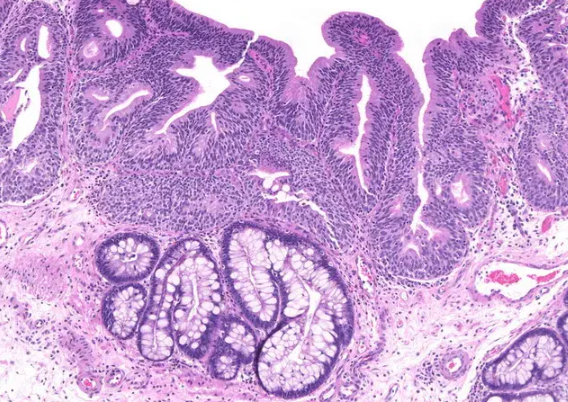

장상피화생은 위 점막이 장 점막처럼 바뀌는 현상입니다. 위 점막은 본래 산성 환경에서 잘 버틸 수 있도록 구성되어 있지만, 오랜 기간 위염이나 헬리코박터균 등에 의해 자극을 받을 경우 장 세포처럼 변형되기도 합니다. 이는 위의 방어기능이 약해졌다는 신호로 볼 수 있지요.